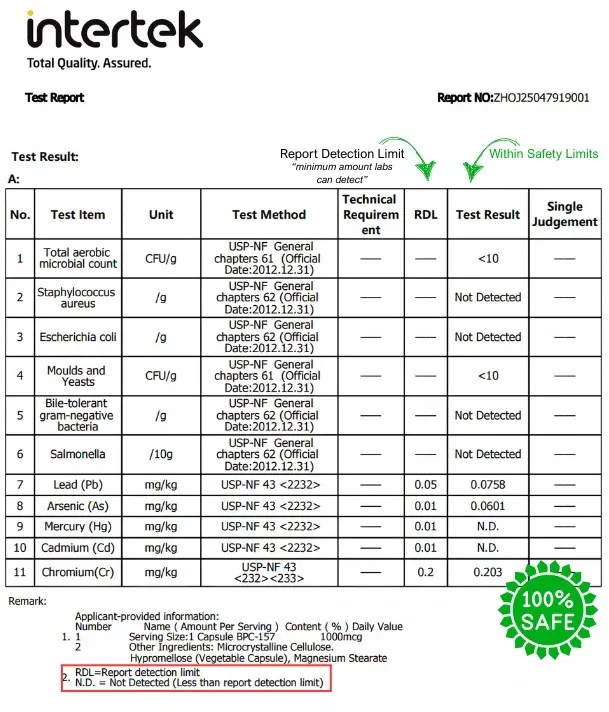

BPC-157 is a synthetic peptide originally derived from a protective protein in the stomach. It’s known for its potential to accelerate healing, support joint and muscle recovery, and reduce inflammation. Many people use it to support injuries, gut health, and overall tissue repair — making it popular among athletes, biohackers, and those seeking faster recovery.